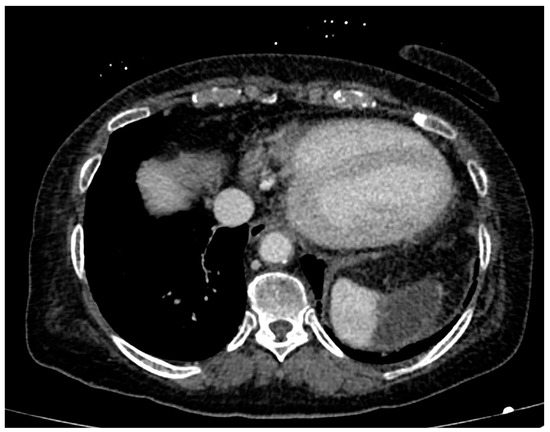

- Focal ischemia of the splenic parenchyma in two patients (18.2%) (Figure 4);